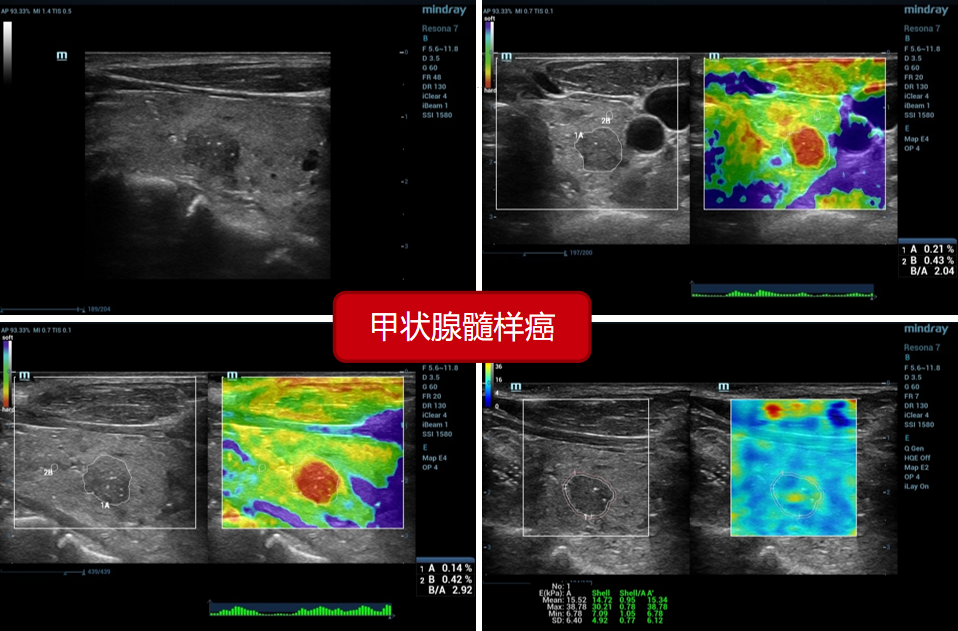

3、甲状腺髓样癌(病例来源上海六院):

3、甲状腺髓样癌(病例来源上海六院):